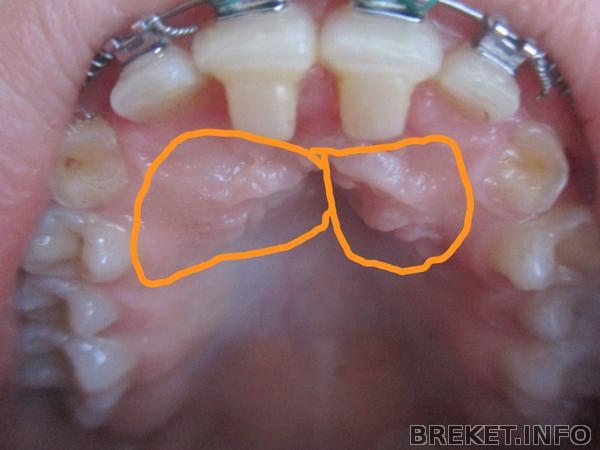

те самые ретинированные клыки которые не хотят вылазить .